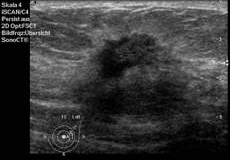

Die Mammasonografie erlaubt die Darstellung von zystischen und soliden Herdbefunden, die anhand verschiedener Kriterien hinsichtlich Gutartigkeit oder Bösartigkeit weiter charakterisiert werden. Hierzu werden die Form, Begrenzung, Ausrichtung und Binnenstrukturen von Herdbefunden sowie die umgebenden Gewebestrukturen beurteilt. Zusammen mit der farbkodierten Dopplersonografie (Darstellung von kleinen Blutgefäßen) ermöglicht die Mammasonografie eine Differenzierung zwischen gutartigen und bösartigen Veränderungen. Mit Hilfe moderner Ultraschallgeräte lassen sich Herdbefunde ab einer Größe von 5mm nachweisen.

Wesentliche Voraussetzungen für eine qualitativ hochwertige Mammasonografie sind moderne Ultraschallgeräte mit speziell für die Brust konzipierten linearen und hochauflösenden Schallköpfen mit hohen Frequenzen (› 7,5 MHz) und damit hoher räumlicher Auflösung. An unserem Institut steht für die Mammasonografie ein solches Gerät zur Verfügung (HDI 5000, Phillips).